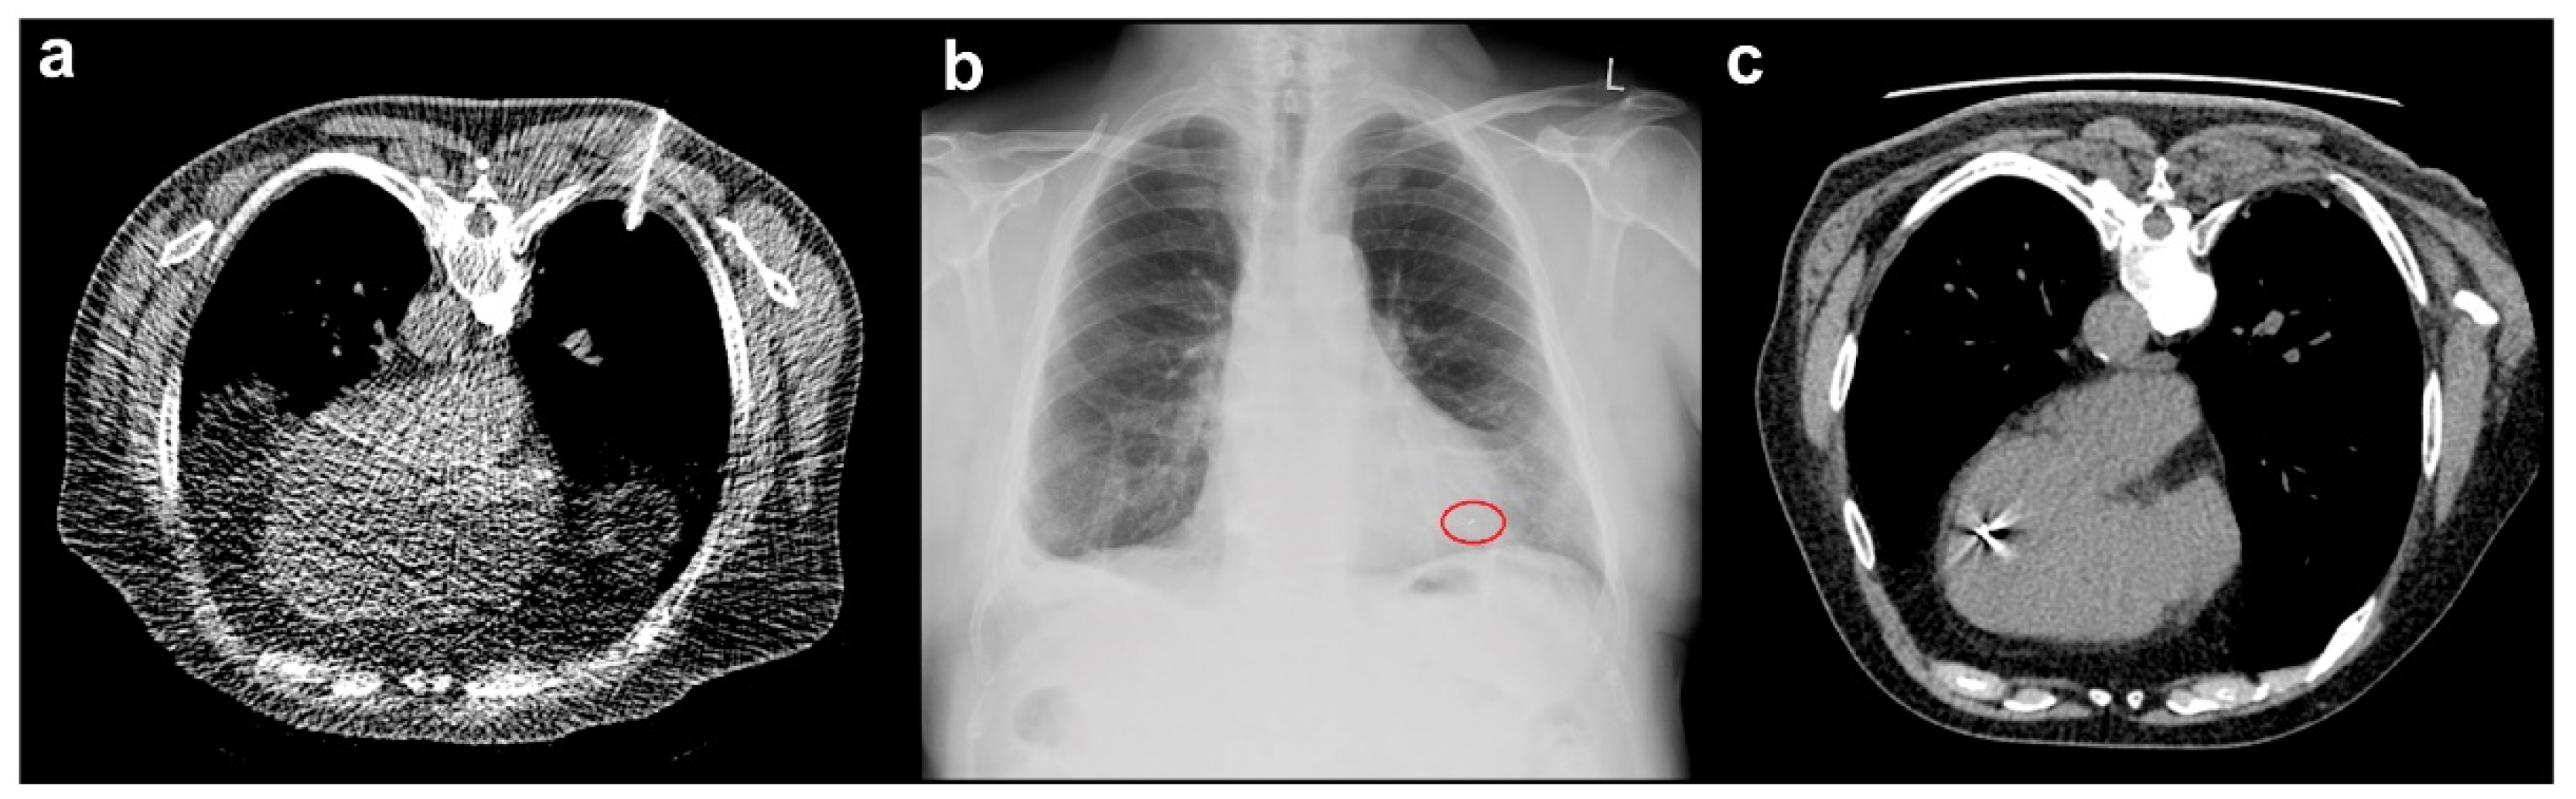

3.2.1. Analysis of Modality-Associated Complications

3.2.2. Locations of Complications

3.3. Marker Migration

4.1. Thoracic Complications